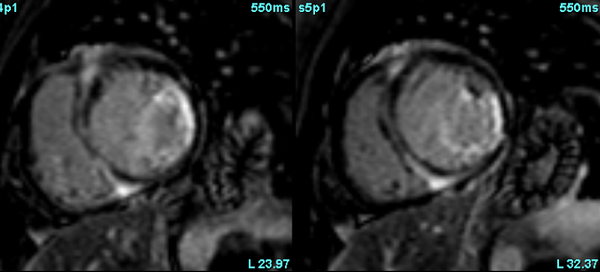

Amyloidosis